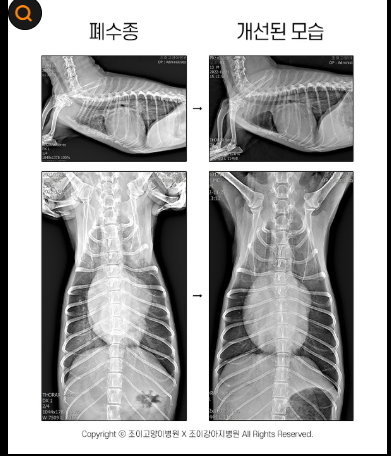

특히 슬개골 탈구,폐렴,기관허탈,간경화,심장 질환처럼 치료 비용이 높은 질병에 대비하기 위해 미리 보험을 준비해 두는 것이 반려

견 건강 관리에 도움이 될 수 있습니다.